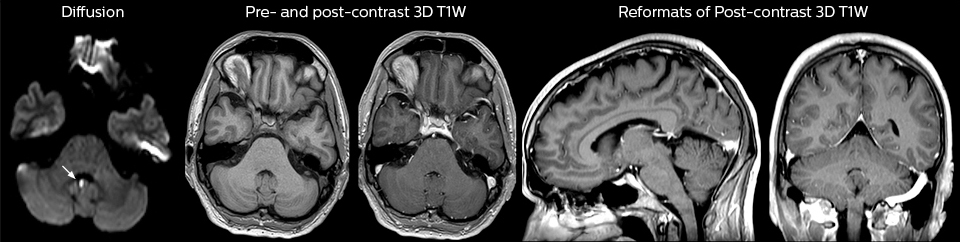

A range of protocol sheets was developed to help ensure that referring physicians order the most appropriate MRI exam. The optimized MRI protocols also include 3D contrast-enhanced imaging, allowing neurosurgeons to comfortably use the isotropic data in the operating room while performing stereotaxic surgery.

“One of the most important decisions an ED physician has to make is to admit or discharge their patient. So a physician who is better informed by an MRI exam can make this decision with more confidence. By converting to a test that has a far better potential to identify issues, physicians get a better and more certain diagnosis."

“Our results show that a dedicated MRI in the ED can be effectively implemented; patient turnaround times with MRI were on par with CT. Interestingly, even though the MRI exam protocols were shortened, this robust yet rapid scanning still yielded good quality images, further improving our workflow and almost eliminating the need for repeat scans or follow-up scans. So, we’re heading towards first time right imaging,” says Dr. Karis.